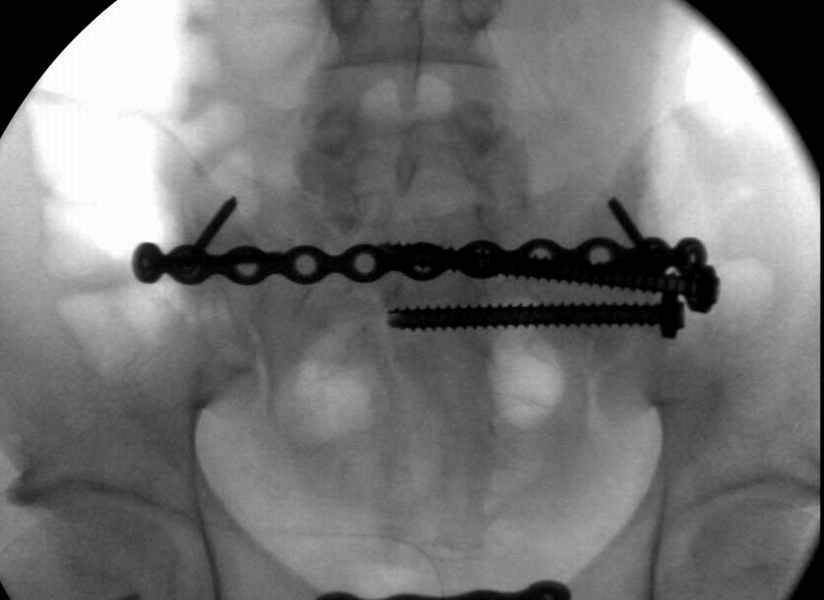

Здесь слайды случая больного с политравмой, включающей сегментарный перелом бедра и повреждение таза с нарушением тазового кольца, разрыв симфиза и перелома крестца зон 2 и 3.

На множественных слайдах важные моменты операции. Хотел бы подчеркнуть, как важно иметь возможности всех необходимых ренгенограмм, включая компютерную томографию и стандартных внутритазовых рентгенограмм (инлет и оутлет).